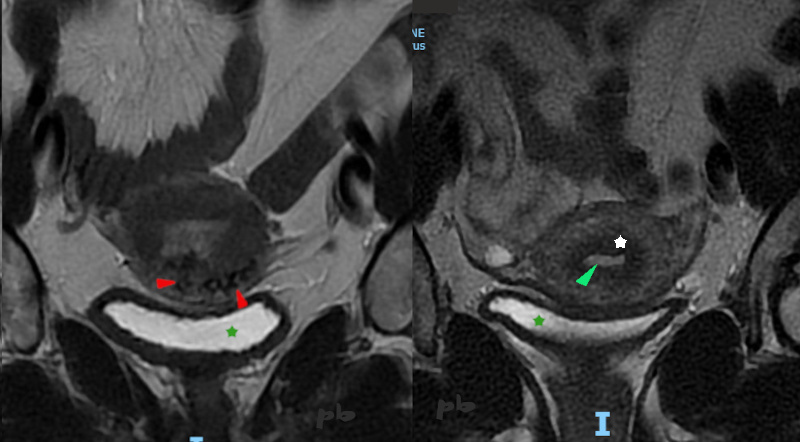

IRM coupes frontales, T2 à gauche et séquence vasculaire injectée (Tricks) à droite.

Fausse couche il y a 2 mois. Traitement médical. Une 1ère échographie avait mis en évidence des résidus avec faible résistance vasculaire et une afférence de l’artère utérine.

Sur les 2 coupes, images de vide de signal (noires ►) dans l’endomètre : vaisseaux à flux rapides.

Présence d’images identiques dans le myomètre (►). A ce niveau, le myomètre s’opacifie plus vite (★) que dans le reste de l’utérus.